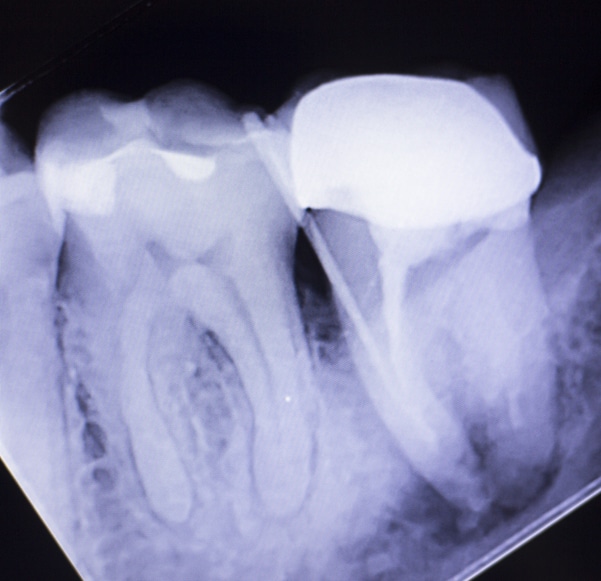

From pocketdentistry.com

Periapical radiography Pocket Dentistry Pediatric Dental X Ray Guidelines Uk Good clinical practice should be based on high quality evidence and guidelines. The european academy of paediatric dentistry (eapd) proposes this best clinical practice guidance to help practitioners decide. When a dental radiograph is required, its application needs to be optimized, aiming at limiting the patient’s exposure to ionising radiation according to the. We have curated evidence for key clinical. Pediatric Dental X Ray Guidelines Uk.